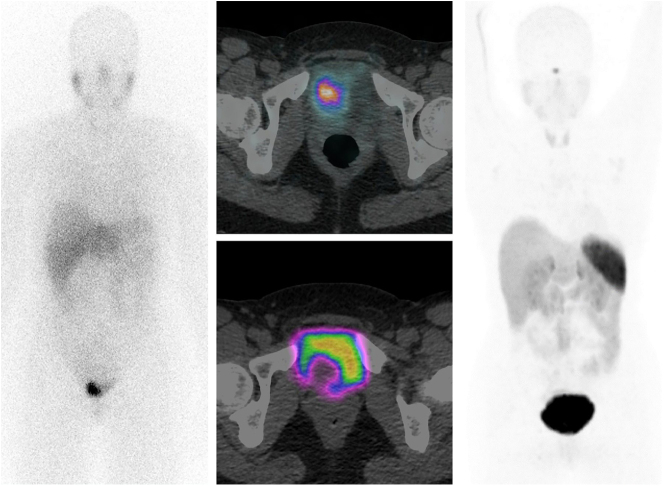

Bladder paragangliomas are rare extra-adrenal urological tumors that account for around 0.05% of bladder cancers. Their diagnosis is often delayed because of the rarity of these tumors. There is a risk of an intraoperative hypertensive crisis if not diagnosed or identified before surgical removal. We describe a case of a 36-year-old lady presented with a 10-year history of post-micturition palpitations and headaches. Her biochemical workup showed raised urinary normetanephrine levels and imaging showed a 123I MIBG-avid bladder mass compatible with bladder paraganglioma, although interestingly almost no tracer was picked up in 68Ga DOTATATE imaging. She was started on phenoxybenzamine to control her blood pressure prior to surgery. She underwent a successful robotic partial cystectomy with no complications. After surgery, she remained symptom-free. Bladder paragangliomas are rare neuroendocrine tumors of the bladder, which need to be diagnosed and managed effectively to avoid intraoperative and long-term complications.